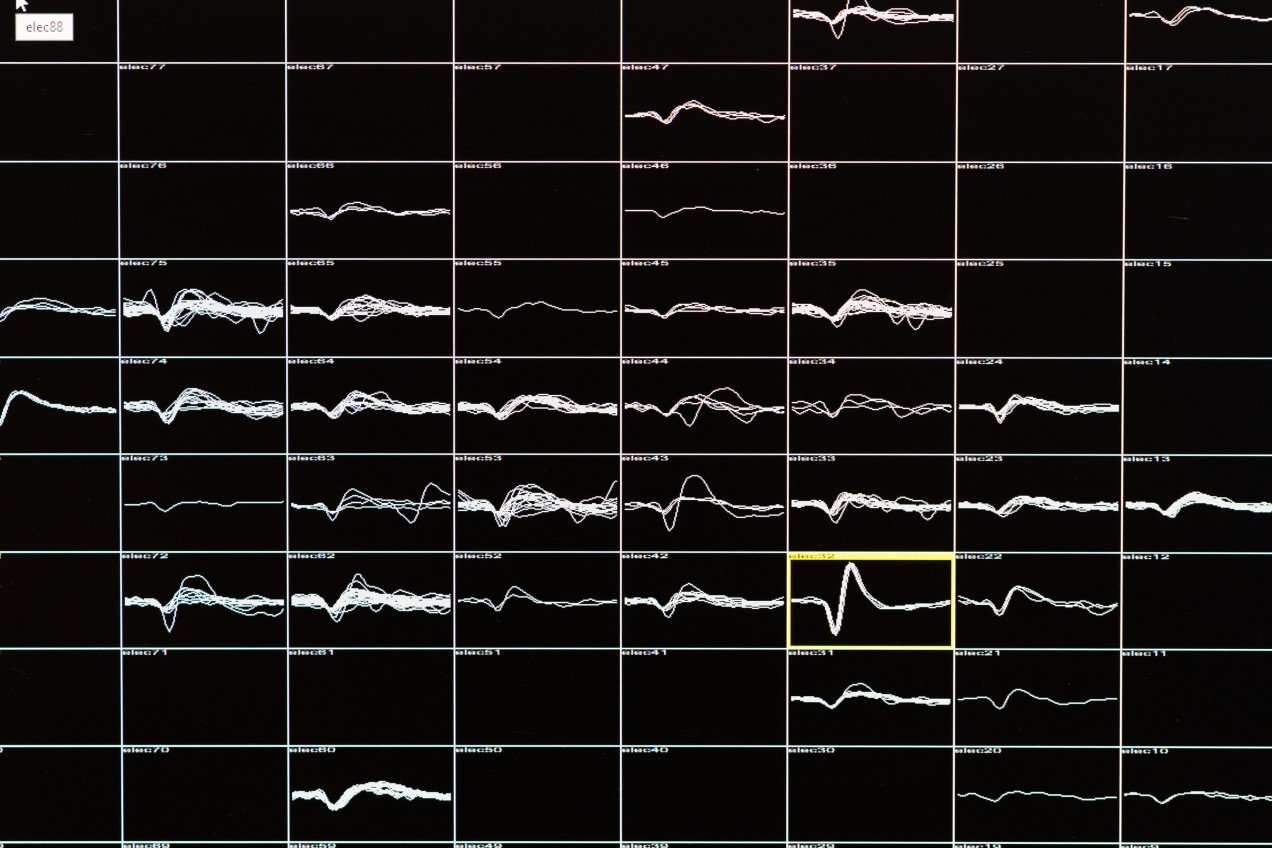

Но после 16 лет тьмы Гомез предоставили шестимесячное окно, во время которого она могла видеть подобие окружающего мира в очень низком разрешении, представленное жёлто-белыми точками и фигурами. Это стало возможным благодаря модифицированным очкам с крохотной камерой. Устройство подключено к компьютеру, обрабатывающему картинку в реальном времени и превращающему её в электрические сигналы. Свисающий с потолка кабель соединяет систему с разъёмом, встроенным в затылок Гомез, подключённому к имплантату со 100 контактами, помещённому в зрительную кору задней части её мозга.